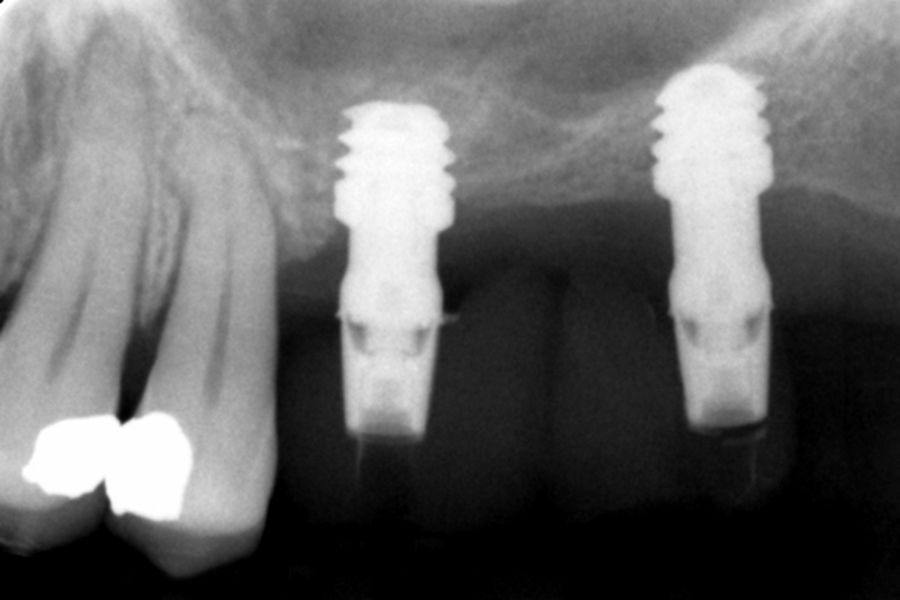

All implants were rehabilitated in two phases and all of them were ferulized to other implants in the rehabilitation. In all cases, screwed prostheses of more than one implant with intermediate elements (transepithelial) were performed, ferulizing to other implants with a length of 4.5 or 5.5 mm. In all situations, a progressive prosthesis load was carried out 6 months after insertion of the implant consisting of a provisional structure finished in resin to move to a definitive metal-ceramic prosthesis. In all cases, the initial transepithelial are preserved to maintain the hermeticity achieved in the first phase of prosthesis manufacture.

Figures 2-19 show one of the cases included in the study.